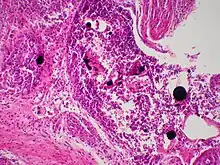

| Cutaneous mercury granuloma is a rare disorder caused by the introduction of elemental Hg into skin. | |

Mercury granulomas is the result of mercury exposure, a skin condition characterized by foreign-body giant cell reaction.[1]: 46